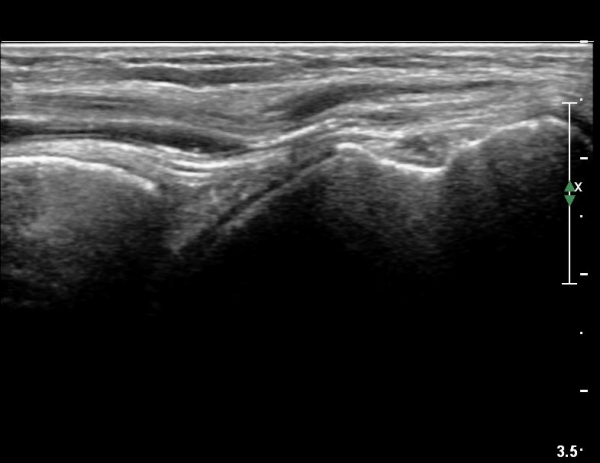

ÃÊÀ½ÆÄ °Ë»ç

CT : avulsion fracture of distal tibia at distal tibiofibulat ligament insertion.